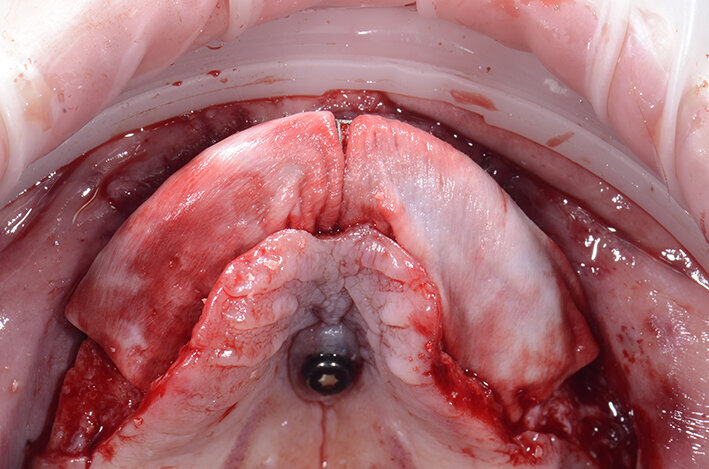

L’incisione primaria del lembo è fondamentale. Devono essere attentamente valutati gli esiti cicatriziali presenti in casi di atrofie così marcate. In questo caso, e in generale nei casi di arcate edentule si tende a fare una incisione in cresta. Il nostro obiettivo deve essere quello di creare e quindi lasciare una porzione palatale del lembo primario adeguata alla ricopertura della griglia perché la parte del palato non è estendibile (Fig. 9). Nelle zone in cui il difetto è più marcato le incisioni si spingono verso la parte vestibolare del lembo primario; in questo modo lasciamo tanto tessuto palatale mentre la parte vestibolare del lembo sarà alla fine dell’intervento riadattata attraverso tecniche di rilascio del lembo dai piani muscolari sottostanti e dal periostio. Il lembo primario vestibolare deve essere sbrigliato dagli eventuali esiti cicatriziali presenti effettuando manovre con molta attenzione per non lacerare il lembo.

Quello che troviamo è un’atrofia marcata in senso orizzontale nella zona della pre-maxilla che si estende anche nei settori latero-posteriori. Terminata la parte più importante dell’intervento ci dedichiamo a verificare il fit della griglia customizzata. È sorprendente ogni volta constatare l’alta affidabilità del posizionamento tridimensionale (Fig. 10). Il riempimento della griglia viene effettuato con osso autologo raccolto con Safe Scraper e con pinze ossivore che ci consentono anche di regolarizzare la cresta nella zona di intervento, miscelato al 50% con osso Bovino Deproteinizzato (Geistlich Bio-Oss, Geistlich Pharma).